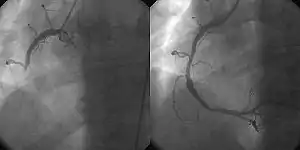

- Percutaneous coronary intervention (PCI/Coronary angioplasty)

- the use of angioplasty for the treatment of obstruction of coronary arteries as a result of coronary artery disease. A deflated balloon catheter is advanced into the obstructed artery and inflated to relieve the narrowing; certain devices such as coronary stents can be deployed to keep the blood vessel open. Various other procedures can also be performed at the same time. After a heart attack, it can be restricted to the culprit vessel (the one whose obstruction or thrombosis is suspected of causing the event) or complete revascularization; complete revascularization is more efficacious in terms of major adverse cardiac events and all-cause mortality.[4]

- PCI is also used in people after other forms of myocardial infarction or unstable angina where there is a high risk of further events. The use of PCI in addition to anti-angina medication in stable angina may reduce the number of patients with angina attacks for up to 3 years following the therapy,[5] but it does not reduce the risk of death, future myocardial infarction, or need for other interventions.[6]